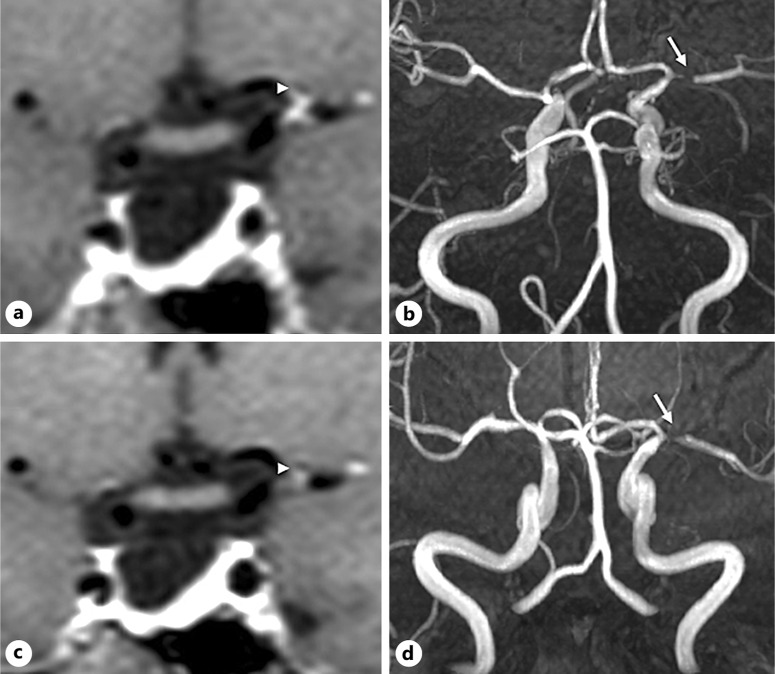

Results: We identified 10 patients (9 males) with FCA giving an incidence rate of 2.8 per 1,000 person-years. Nine patients had an ischemic presentation (transient ischemic attacks = 5, minor strokes = 3, and major stroke = 1), while 1 patient had a cortical subarachnoid hemorrhage. The supraclinoid ICA and proximal middle cerebral artery (MCA) were the most common segments involved. Nine patients were treated with antiplatelets, and 3 received additional steroids. All cases underwent MRVWI, with concentric wall enhancement noted in most (80%). Follow-up imaging showed improvement in stenosis in 2 patients and a reduction in vessel wall enhancement in 3 patients. Except for the patient with a major stroke, all others had excellent short- and long-term outcomes with no recurrence of ischemic events. The presence of vessel wall enhancement did not predict short- or long-term outcomes.

Conclusion: FCA is a rare cause of young stroke that preferentially involves the supraclinoid ICA and proximal MCA with excellent outcomes. MRVWI can be useful in ruling out mimics, but the presence of contrast enhancement did not predict outcome.